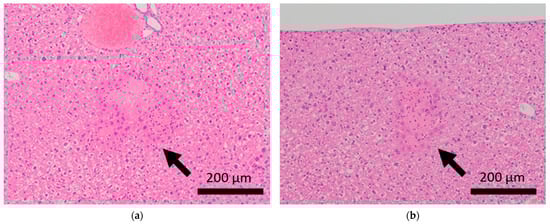

Histopathological features of the livers of BALB/c mice. Arrows indicate focal necrosis in the livers of control mice (a,b), whereas this was not observed in mice subjected to sCSDS (c,d).

Figure 4.

Brain microhemorrhage was observed in sCSDS mice but not in control mice (Control: 0.00% vs. sCSDS: 33.33%, p = 0.26). Calcification of the epicardium in the heart was observed in both control and sCSDS mice (Control: 80.00% vs. sCSDS: 44.44%, p = 0.30). Mild fibrosis in the heart was observed only in the sCSDS mice (Control: 0.00% vs. sCSDS: 77.78%, p = 0.02). Interestingly, focal necrosis in the liver was observed only in control mice, and not in sCSDS mice (Control: 100.00% vs. sCSDS: 0.00%, p < 0.01). In the spleen, extramedullary hematopoiesis was observed in both groups (Control: 60.00% vs. sCSDS: 100.00%; p = 0.11). Further, lung hemorrhage was observed in both groups (Control: 80.00% vs. sCSDS: 55.56%, p = 0.58).

Focal necrosis without inflammation was found in the livers of control mice but not in those of sCSDS mice (Table 2 and Table S1, and Figure 3). Spontaneous necrosis of the liver is frequently observed in healthy control rodents and may be induced by local hypoxia, with focal decreases in blood flow [35]. Interestingly, sCSDS may rescue this pathogenesis in the liver. Therefore, whether sCSDS affects the focal circulation of the liver must still be elucidated.